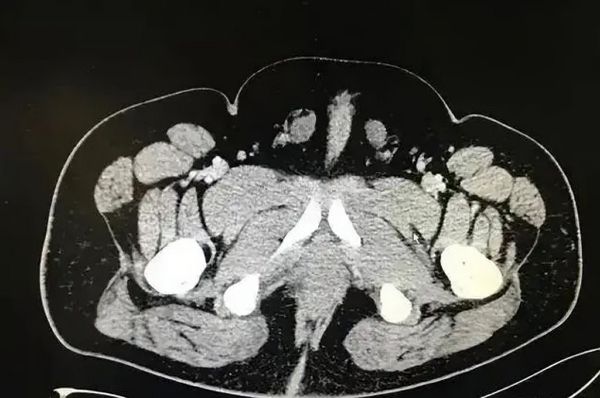

사진은 남녀 생식기를 모두 가진 류씨의 엑스레이. /사진=웨이보 캡처 사진은 남녀 생식기를 모두 가진 류씨의 엑스레이. /사진=웨이보 캡처